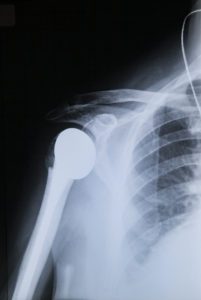

Read MoreHow to Prepare for Shoulder Replacement Surgery

Although many orthopedic conditions and injuries can be treated successfully using nonsurgical methods, a total shoulder replacement may be the best solution for chronic shoulder pain and limited function. Symptoms such as occasional pain, stiffness, numbness, or weakness in the shoulder may be able to be treated nonsurgically with medication and physical therapy, but surgery